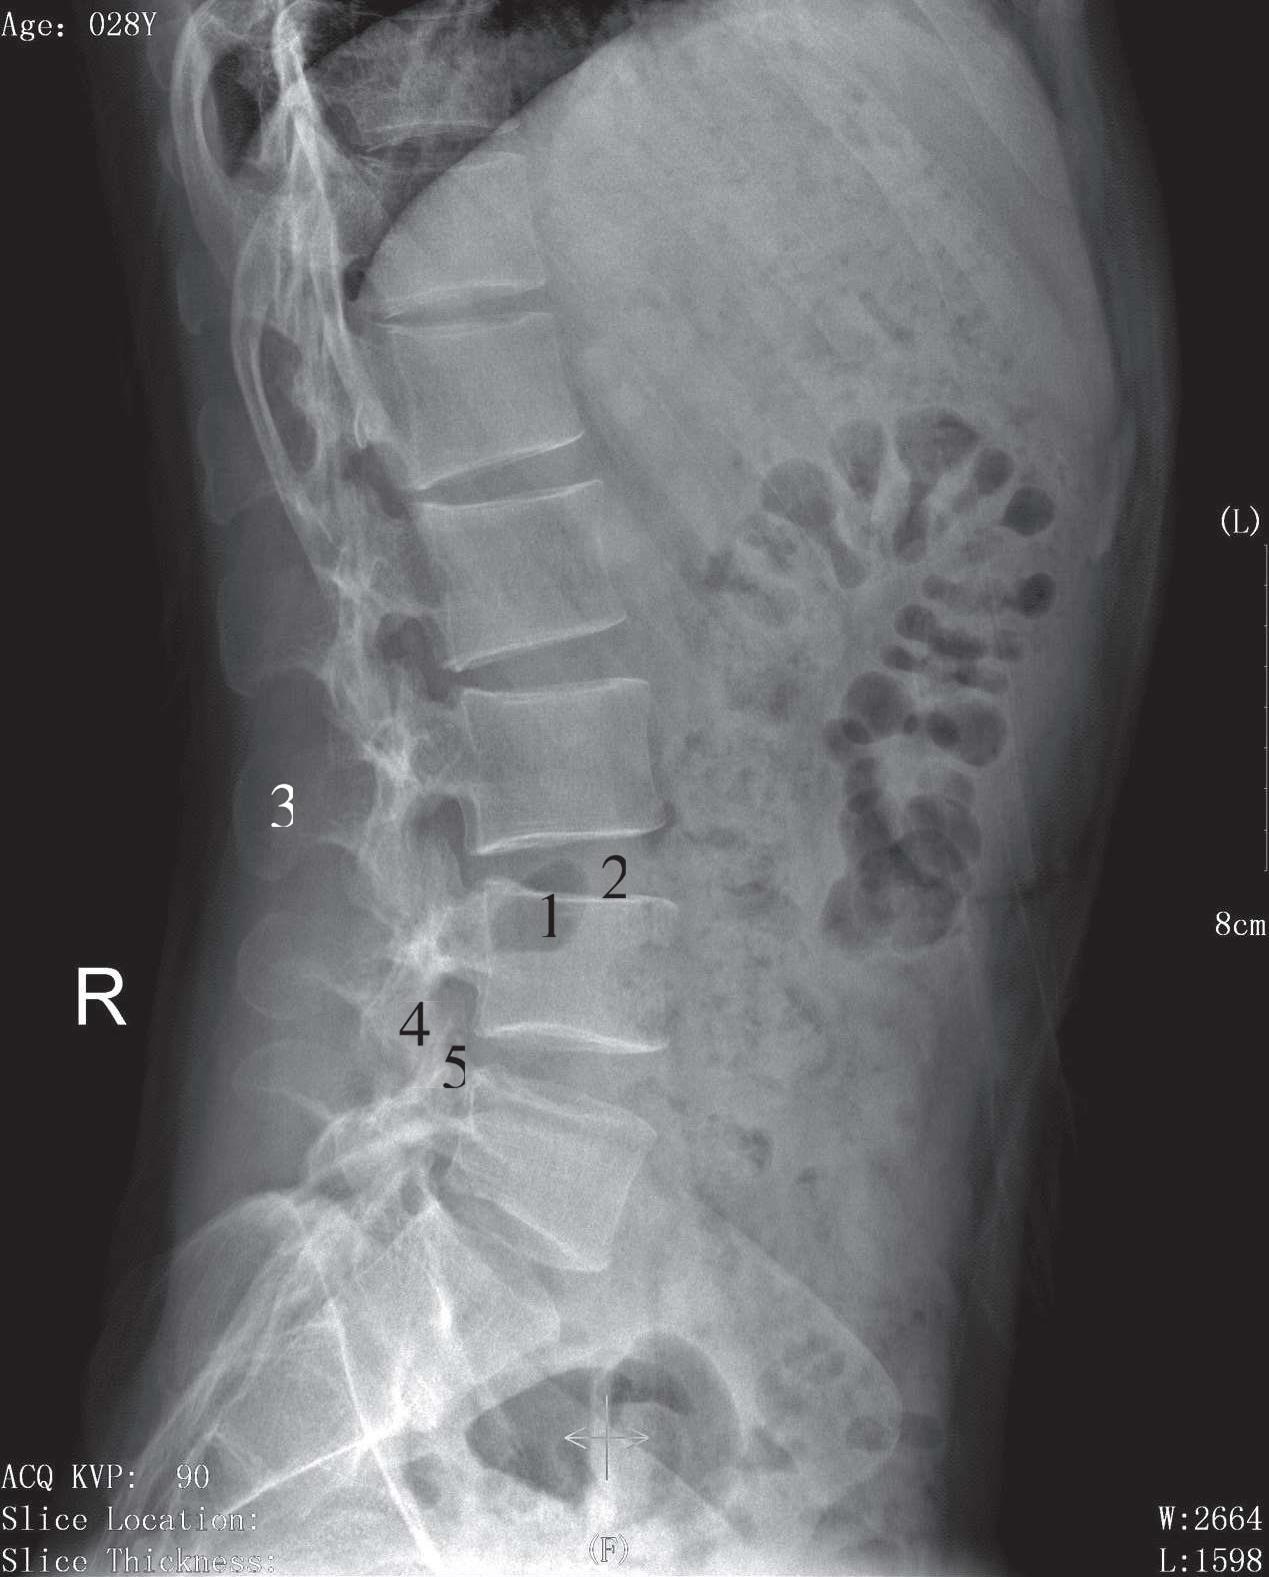

被检者侧卧于检查床上,两臂上举抱头,双下肢屈曲,身体正中矢状面与床面平行,影像接收器上缘包括T 11 ,下缘包括上部骶椎,中心线对准L 3 垂直射入。影像显示腰椎生理性前凸,椎弓根、椎间孔、椎间关节及棘突显示清晰,椎间隙较正位片显示清晰,骨皮质及骨小梁显示良好(图3-14)。

1. 椎体;2. 椎间隙;3. 棘突;4. 下关节突;5. 上关节突

图3-14 腰椎侧位片